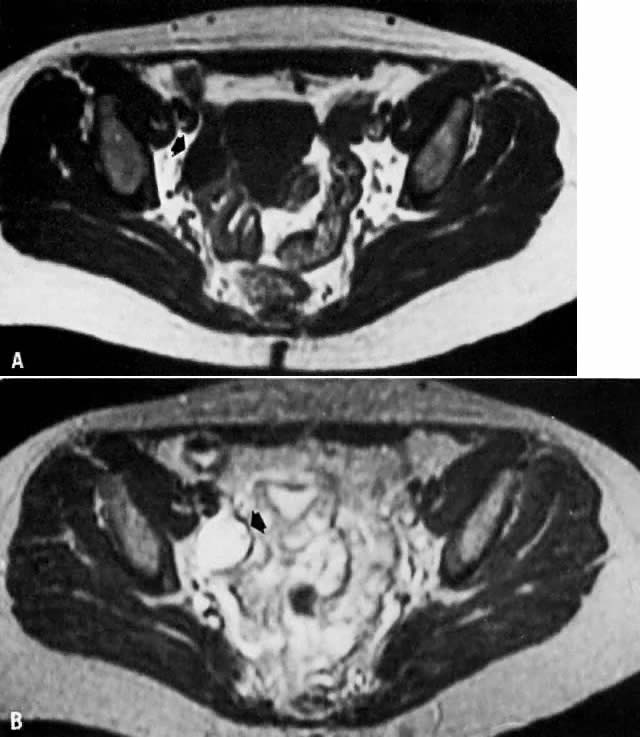

Fig. 8. A. Parametrial extension. Transverse T1-weighted image of a patient with cervical carcinoma extending into the parametrium ( white arrows ). The pelvic side walls ( open arrows) are uninvolved. B. T2-weighted image showing the cancer to have high signal intensity.